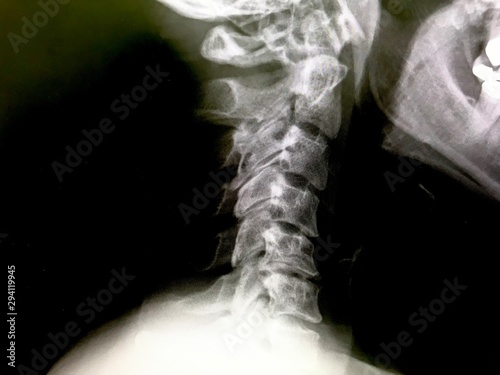

頸椎(首の骨) 頸椎とは 脊椎のくびの部分です. その上に頭蓋骨がつながっています. 脊椎(せぼね)は脊椎動物が全てもっている体を支え る大切なものですが,大きく分けて次の3つの役割が あります. 脊椎(せぼね)の3つの役割 1.体を支える柱. 肺にもやが写る場合に考えられる病気は何があるのでしょうか? May 26, 18 レントゲン肺に白いモヤモヤ レントゲンを撮ると白いモヤが写っており細菌が肺に入ったという説明がありました。 そしてカビなどアレルギー検査もしました。 2日後の今日Dec 04, 06 胸のレドイツの物理学者レントゲンによって発見されたため、レントゲン線といいますが、発見時、正体不明の電磁波だったためxと名づけられました。 肺がん、肺結核、肺炎などの異常があると、白い影として写ります。 高血圧、肥満、首

ストレートネックをレントゲンで見る 僕が参考にしているポイントです 沖縄のストレートネック専門家 肩首こり 首の痛み 緊張型頭痛の整体サロン ラクビヤ

首の骨が逆にカーブしているレントゲン写真 Stock 写真 Adobe Stock

これは 首のレントゲン の写真素材 画像素材 Image